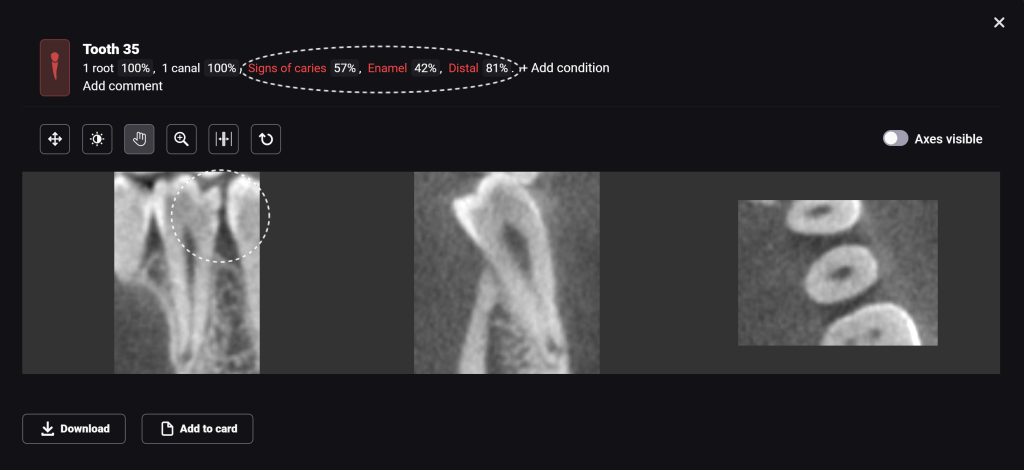

Diagnocat determined not only the presence, but also the localization of the focus of radiolucency of enamel and dentin, which was correctly indicated as “signs of caries” in the report

Please note that despite the fact that the radiolucent area is poorly visible when viewing CBCT, Diagnocat reflected in the report the presence of signs of caries and accurately indicated the localization

The presence of a structured report allows the clinician to set up the patient for timely treatment and build a consistent plan for therapeutic dental treatment